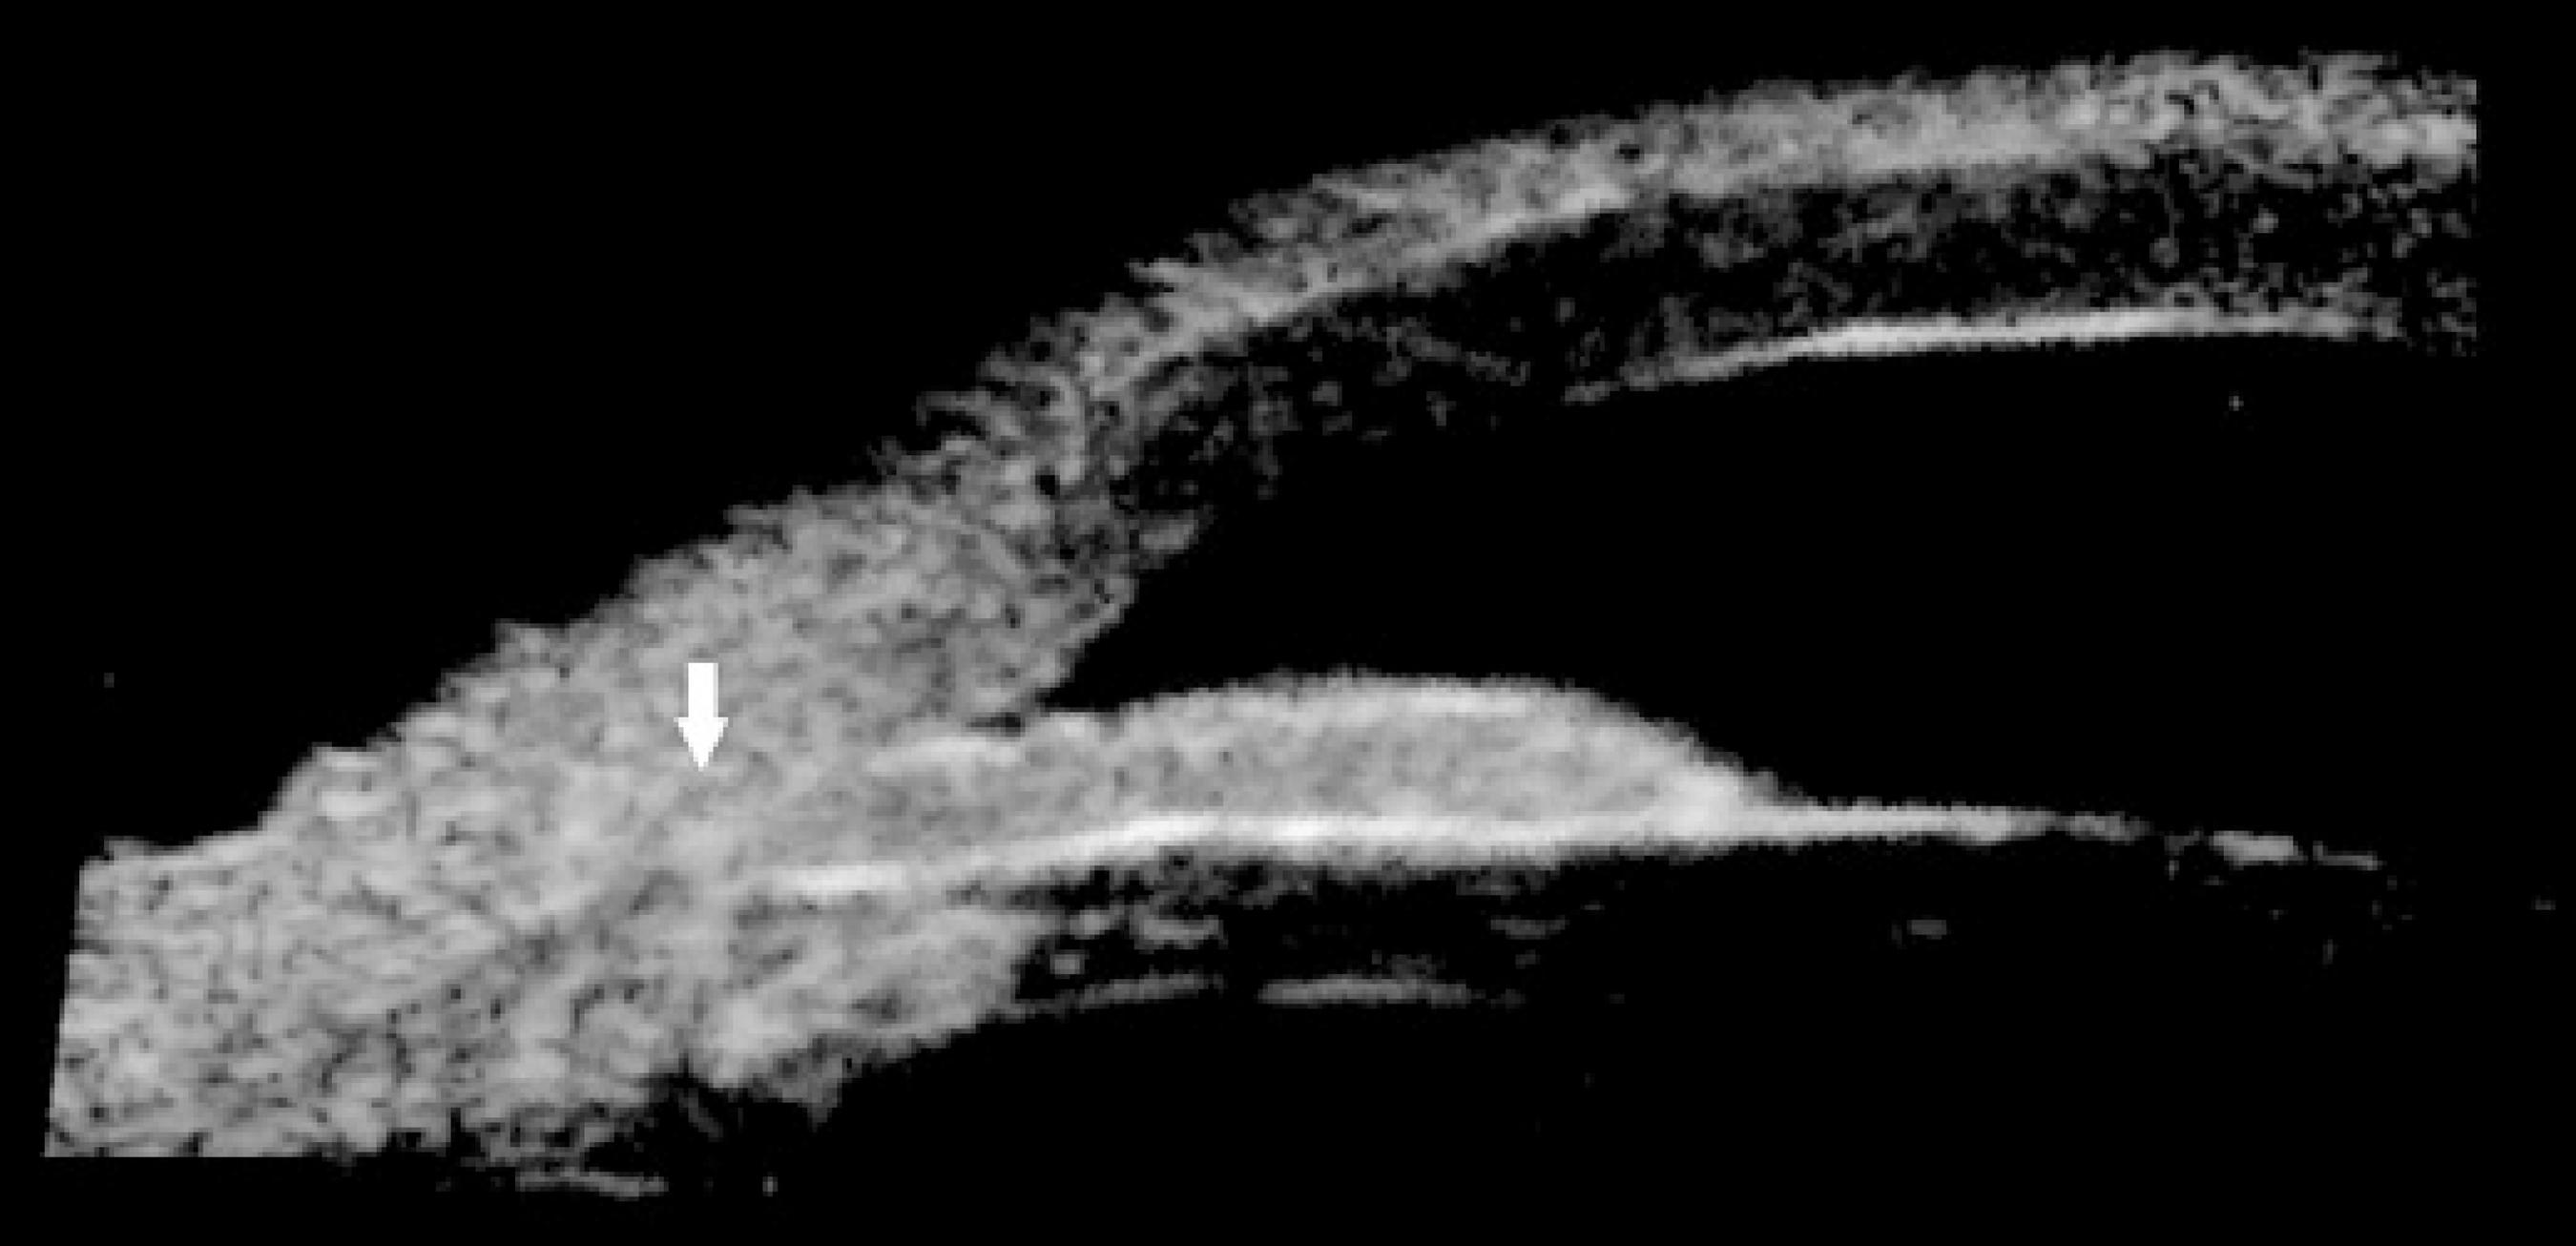

Because the patient did not respond to the treatment, ultrasound biomicroscopy images (Sonomed VuMAX™ II UBM; Sonomed Escalon, Stoneham, MA, USA) were requested, which showed a narrow chamber caused by plateau iris configuration (Figures 1 and 2). Be cause of the relatively narrow anterior chamber, the iris-cornea proximity excluded the possibility of performing laser iridoplasty.

Figure 2 Right eye. Plateau iris configuration: narrow angle (arrow), flat iris, ciliary processes situated anteriorly, and absence of ciliary sulcus.